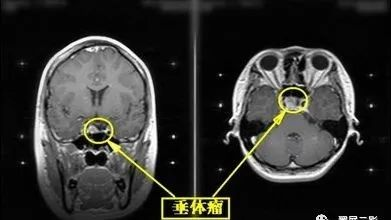

1、垂体腺瘤:大多见于15岁以后患者,常有典型的双颞侧偏盲,视神经萎缩及内分泌改变。X线检查示蝶鞍扩大,鞍底破坏,钙化少见,肿瘤位于鞍内。CT呈等或高密度肿块影,边缘清楚,呈分叶状,瘤内出血为高密度,无钙化,增强不如脑膜瘤明显,但囊变机会多。MRI示等T1、等T2信号,并发出血示T1高信号。微腺瘤尚未强化呈低信号。垂体上缘膨隆,垂体柄移位,是诊断垂体瘤的间接征象。

(垂体腺瘤)